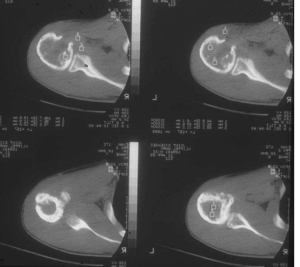

4.x 線表現

(1)ewing肉瘤的放射學特點與其病程相一致,早期,隨著腫瘤組織侵及骨髓,表現為小面積的骨破壞,呈斑片狀,穿鑿樣,邊界不清的溶骨樣破壞,並且與正常骨之間有較廣泛的移形區。

(2)隨著病情的發展,腫瘤侵及骨皮質並通過哈佛管到達並掀起骨膜,但不產生廣泛的皮質破壞。隨著腫瘤對反應性新生骨的不斷破壞而產生特殊的“ 蔥皮”樣骨膜反應。

(3)病灶的不斷擴大,腫瘤突破反應性新生骨而形成大的軟組織腫塊,由於突破通常位於病灶中央區的骨膜,使codman三角向病灶的遠端及近端移位。

(4)偶爾,對於某些發展相對較慢的病灶,骨膜反應能跟上腫瘤生長速度而在溶骨性破壞區外形成完整的、薄的皮質骨,呈多層狀,使骨幹輕度增粗,這種病灶通常無常見的軟組織包塊。

5.其他影像學檢查放射性核素掃描、ct、mri 。